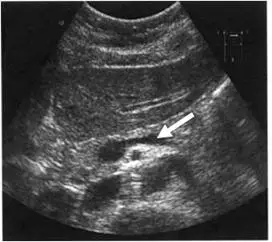

腹部超音波檢查圖像中,箭頭所指之血管為:

圖示為上腹部橫切面(transverse plane)灰階超音波影像,可見多個無回音(anechoic)管狀與圓形結構,為血管之橫斷面或縱斷面。圖中白色箭頭指向一個呈細長橢圓形、管壁薄、無回音的管狀結構,位於影像中央偏左的位置,走向偏水平(橫向),明顯不同於正中線的大型圓形血管(主動脈或下腔靜脈)。

解剖判讀:

- 影像中央可見數個圓形或橢圓形無回音結構,由右至左依序可能包含:下腔靜脈(inferior vena cava, IVC,通常較橢圓且可壓縮)、主動脈(aorta,正中偏左、脈動、壁較厚)、上腸系膜動脈(superior mesenteric artery, SMA,圓形,有亮白色脂肪環繞)

- 箭頭所指結構:走向橫向、偏左側,位於胰臟後方(dorsal to pancreas),符合**脾靜脈(splenic vein)**的典型超音波位置——脾靜脈自脾門(splenic hilum)起始,沿胰體尾部後方由左向右橫行,在胰頭後方與腸系膜上靜脈(sup